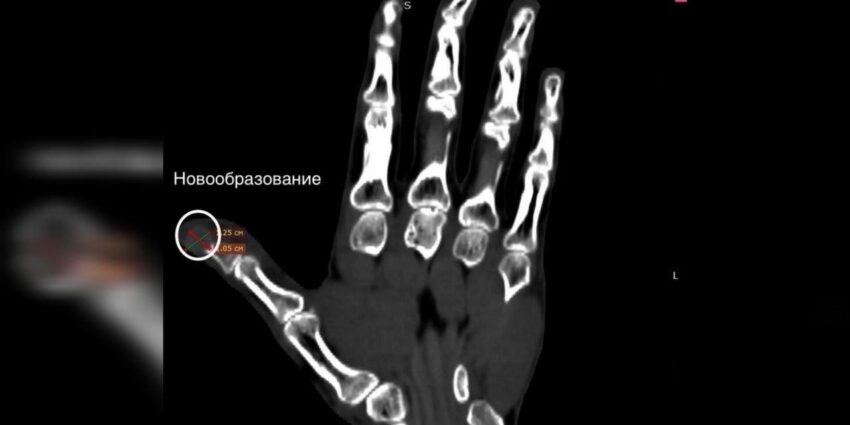

Опухоль на пальце левой руки 47-летнего пианиста удалили хирурги Воронежской областной клинической больницы №1.

На момент обращения к медикам, новообразование, вытеснив мягкие ткани и разрушив часть кости, занимало практически весь ноготь, рассказали в больнице. Для карьеры музыканты это могло стать окончанием профессиональной карьеры.

Биопсия тканей показала, что опухоль доброкачественная. Пианист рассказал, что новообразование появилась два года назад, периодически появлялись боли, иногда рана открывалась.

Удалить опухоль через ноготь, сохранить кость, а также сделать пластику ногтевой фаланги местными тканями смогли хирурги во время этой уникальной операции.